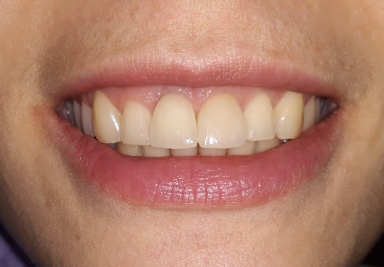

E-max full ceramic crowns

E-max full ceramic crowns on frontal upper incisors